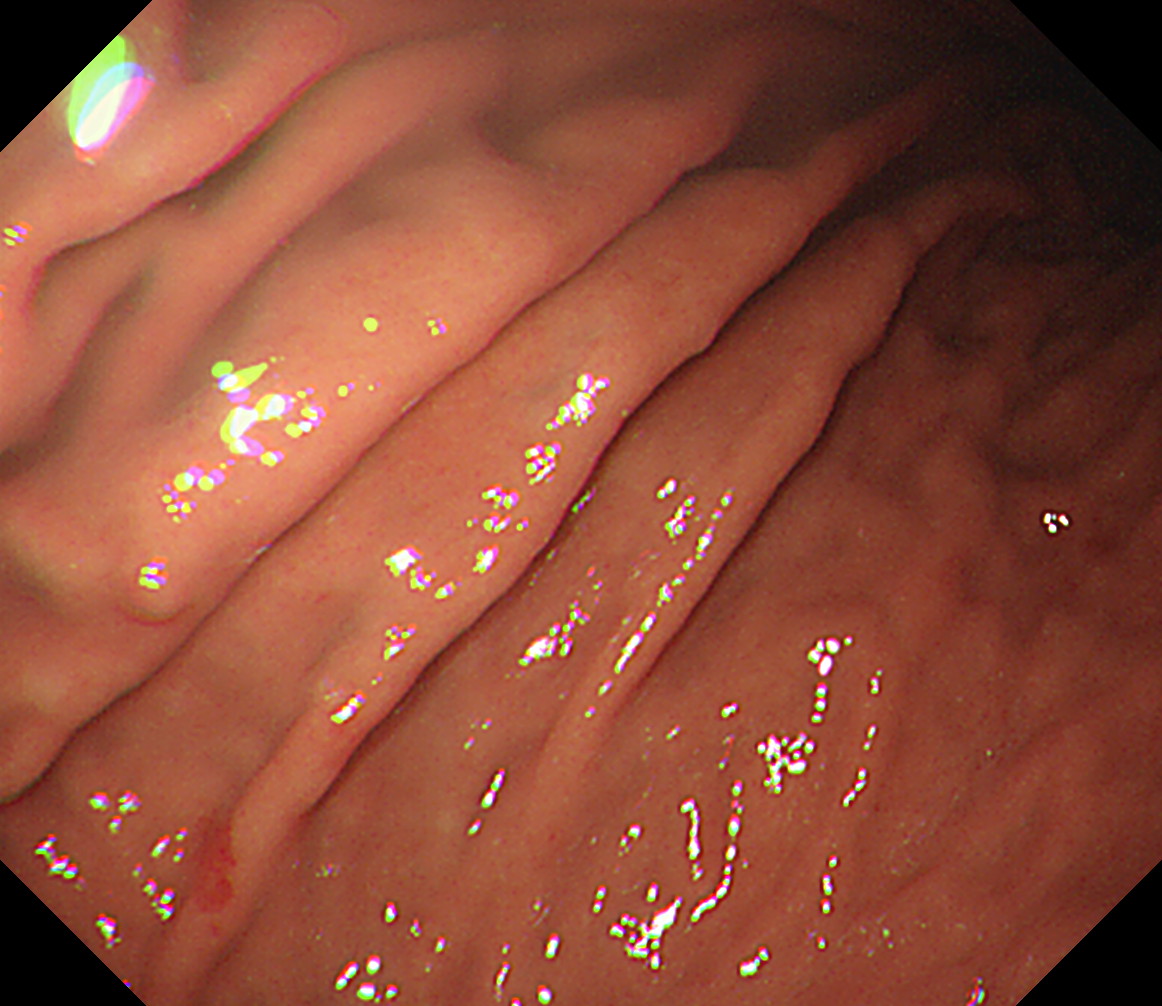

35 体上部大弯 エアーを十分入れて襞の間の病変を見逃さないようにする 体下部小弯